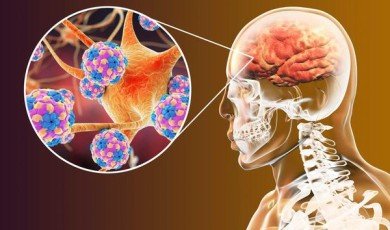

Neurodegenerative Diseases

Neurodegenerative diseases are a group o...

Lecanemab: Why a new Alzheimer's drug has drawn praise and some concern

With the number of Alzheimer’s cases i...